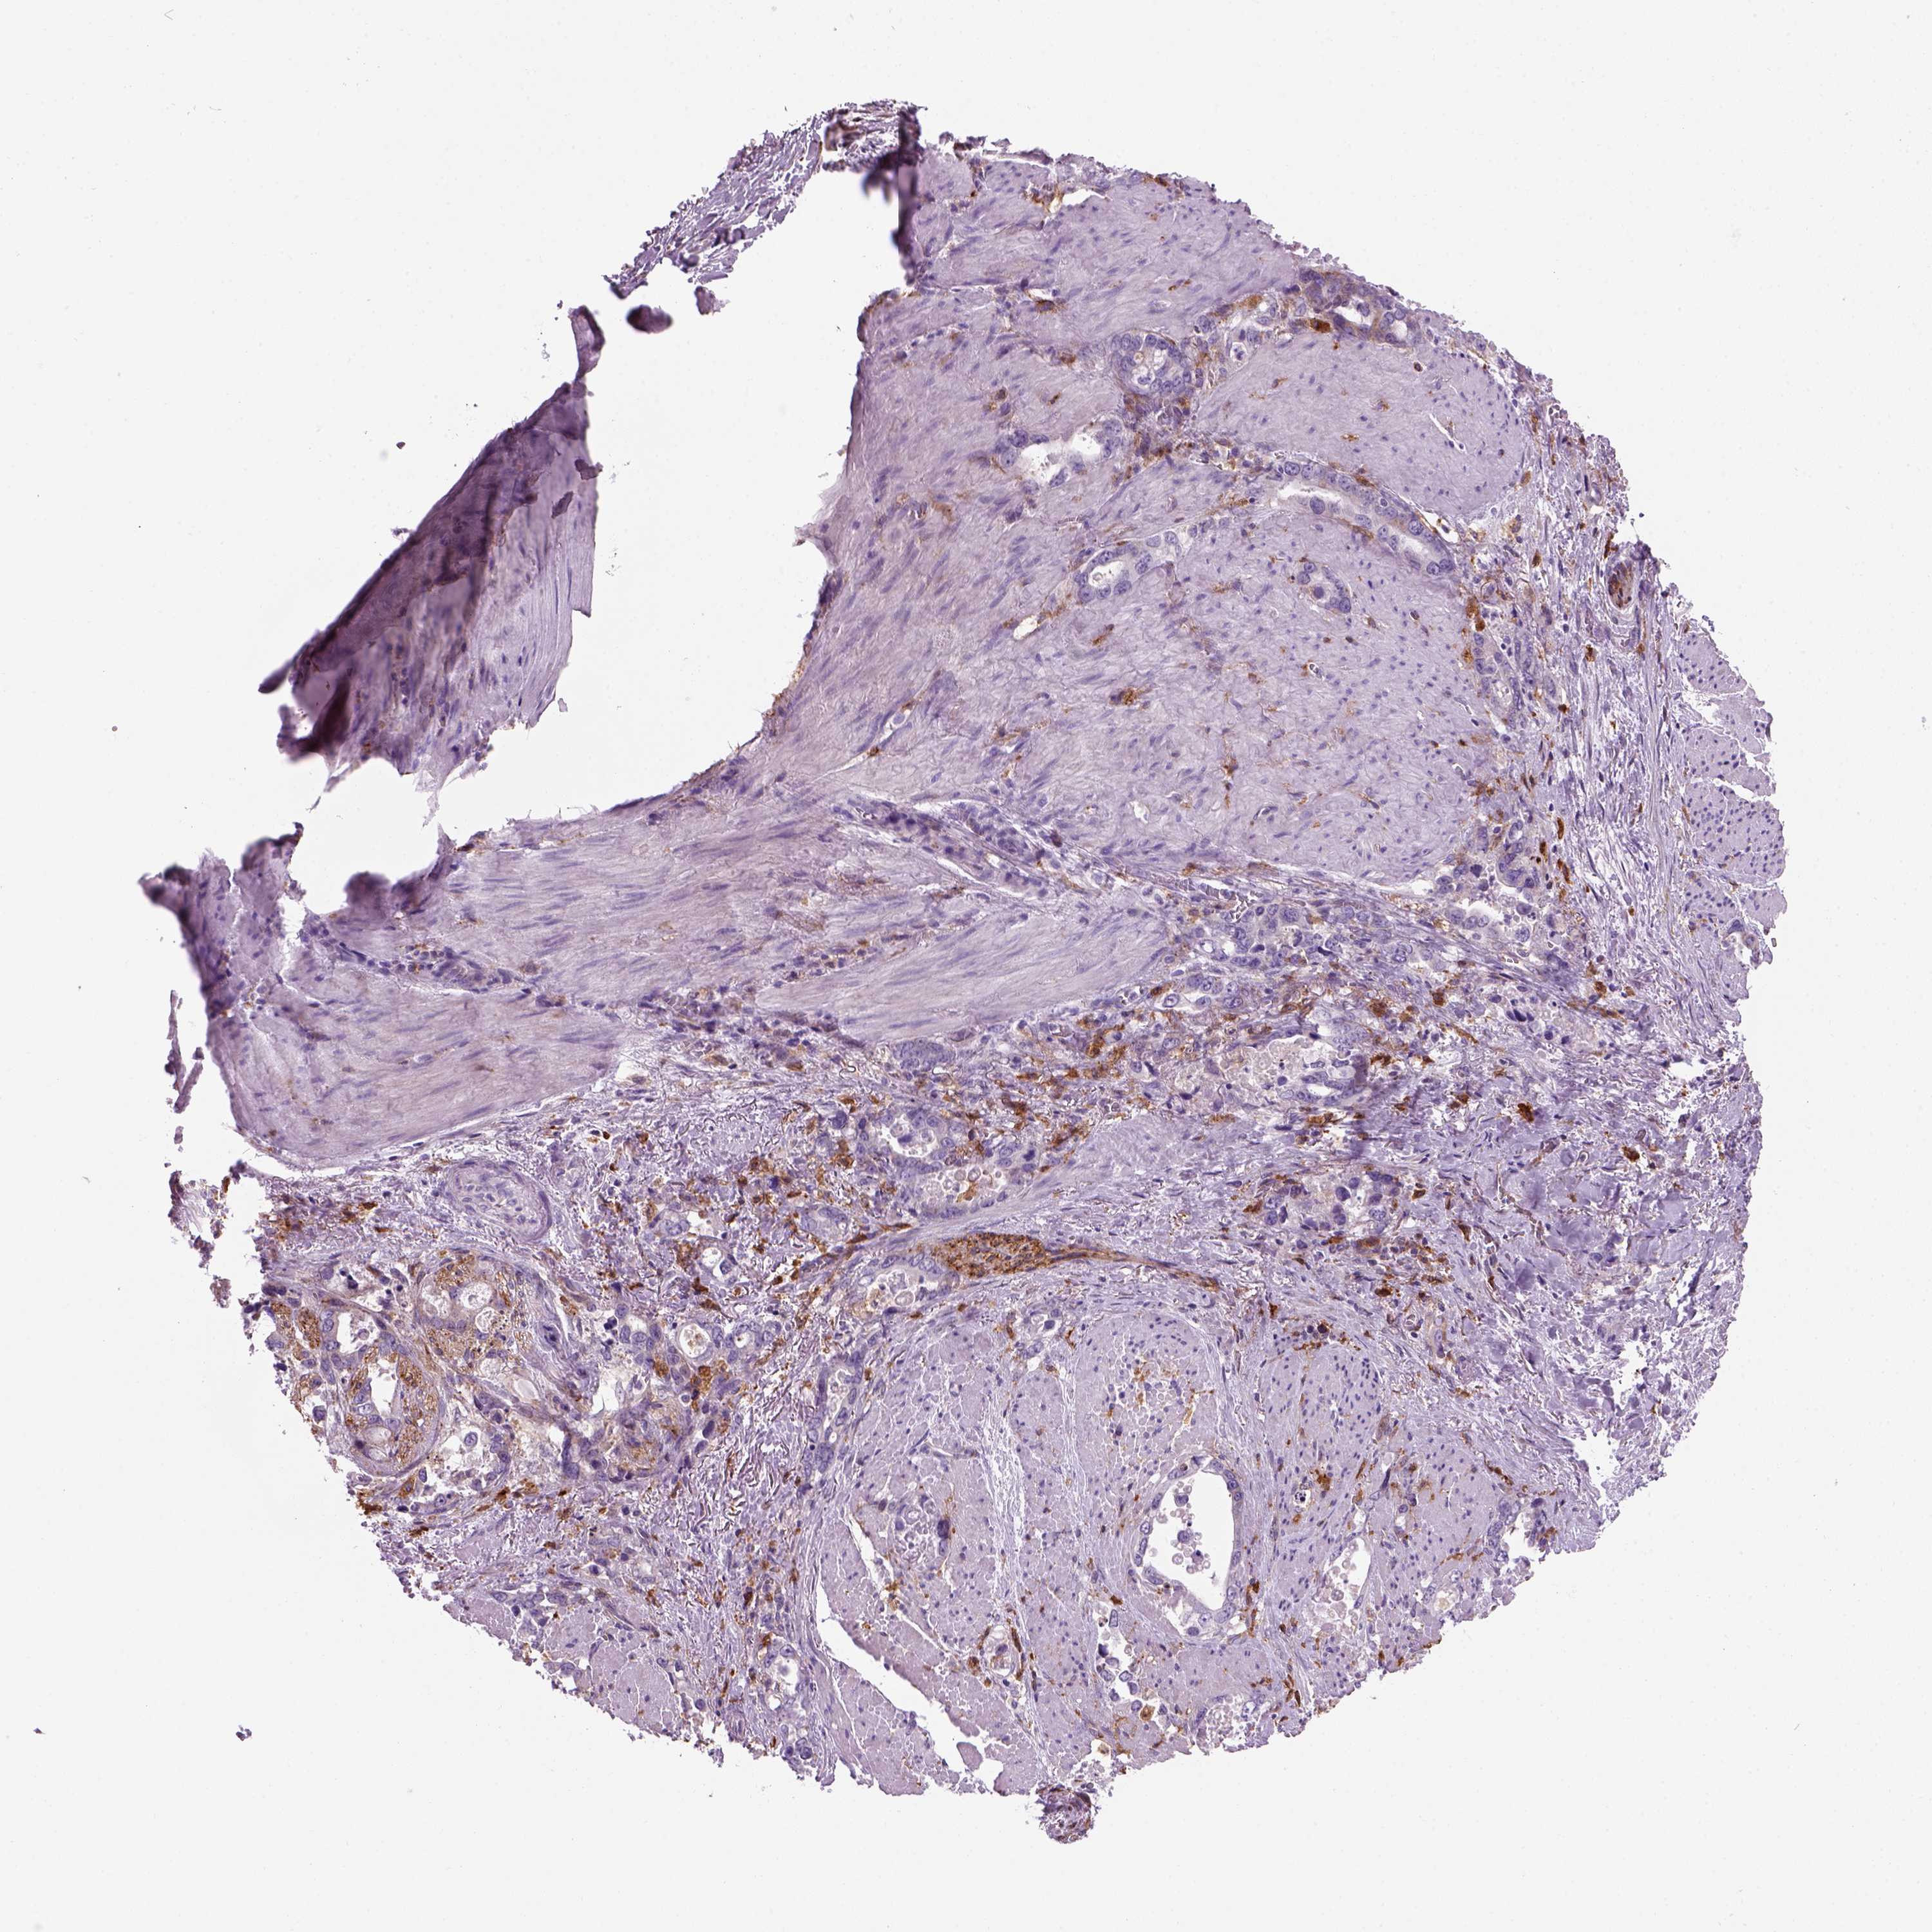

STOMACH CANCER - Protein expressioni

A mouse-over function shows sample information and annotation data. Click on an image to view it in a full screen mode. Samples can be filtered based on level of antibody staining by selecting one or several of the following categories: high, medium, low and not detected. The assay and annotation is described here.

Note that samples used for immunohistochemistry by the Human Protein Atlas do not correspond to samples in the TCGA dataset.

Antibody stainingi

Antibody staining in the annotated cell types in the current human tissue is reported as not detected, low, medium, or high, based on conventional immunohistochemistry profiling in selected tissues. This score is based on the combination of the staining intensity and fraction of stained cells.

Each image is clickable and will lead to virtual microscopy that enables deeper exploration of all samples and also displays staining intensity scores, fraction scores and subcellular localization as well as patient and tissue information for each sample.

Antibody HPA067595

Antibody HPA069443

Antibody CAB022062

Staining

High

Medium

Low

Not detected

Intensity

Strong

Moderate

Weak

Negative

Quantity

>75%

75%-25%

<25%

None

Location

Nuclear

Cytoplasmic/membranous

Cytoplasmic/membranous,nuclear

Adenocarcinoma, NOS

Adenocarcinoma, High grade